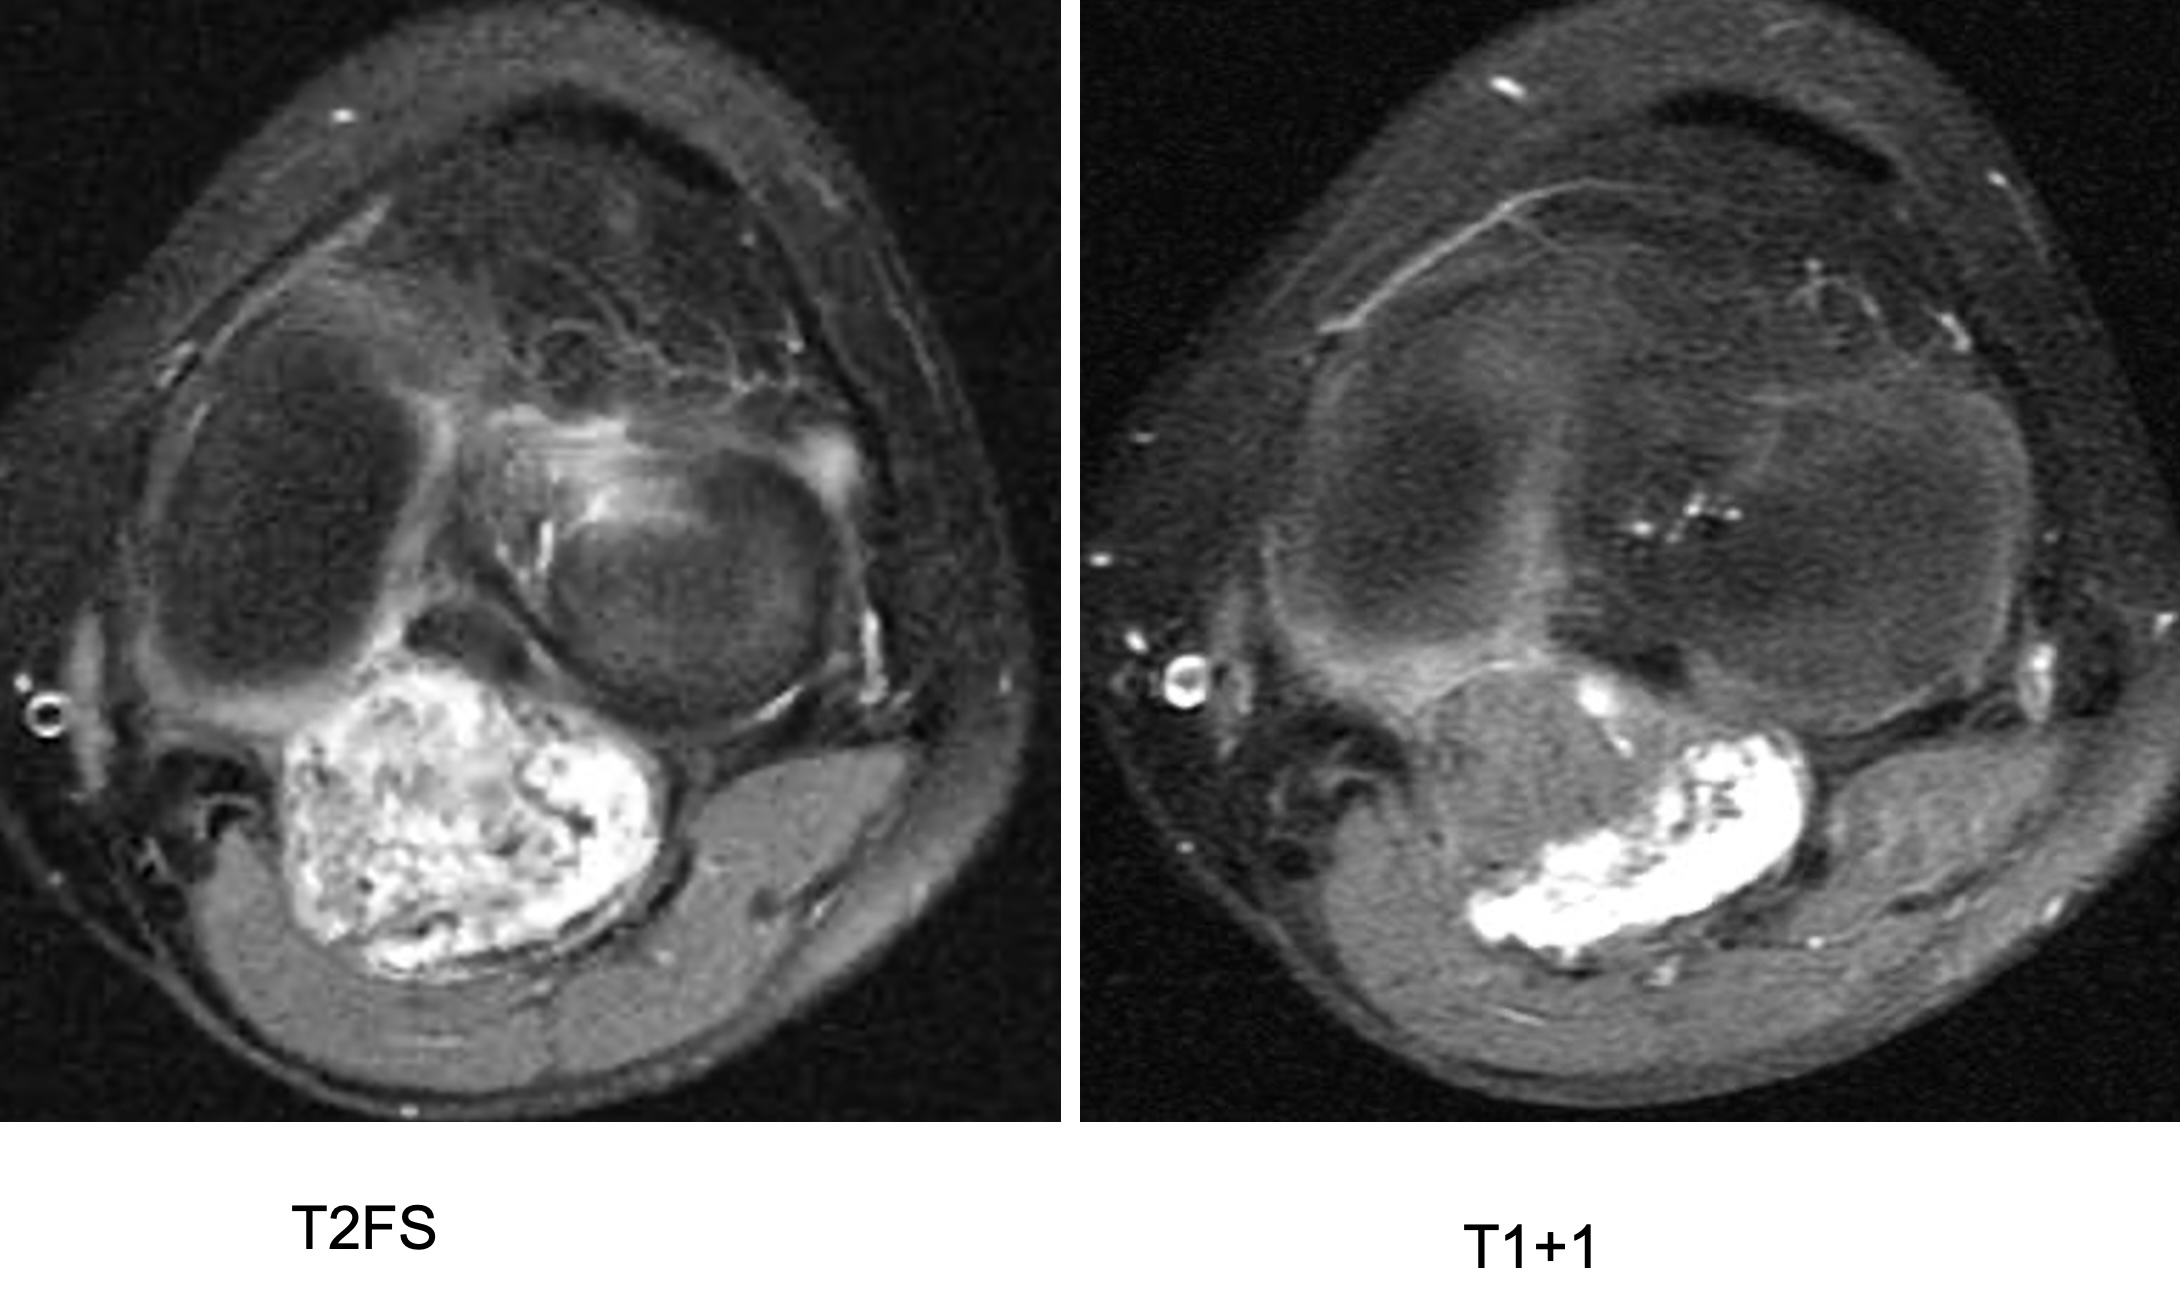

Figure 3 for case Synovial chondromatosis

Figure 3